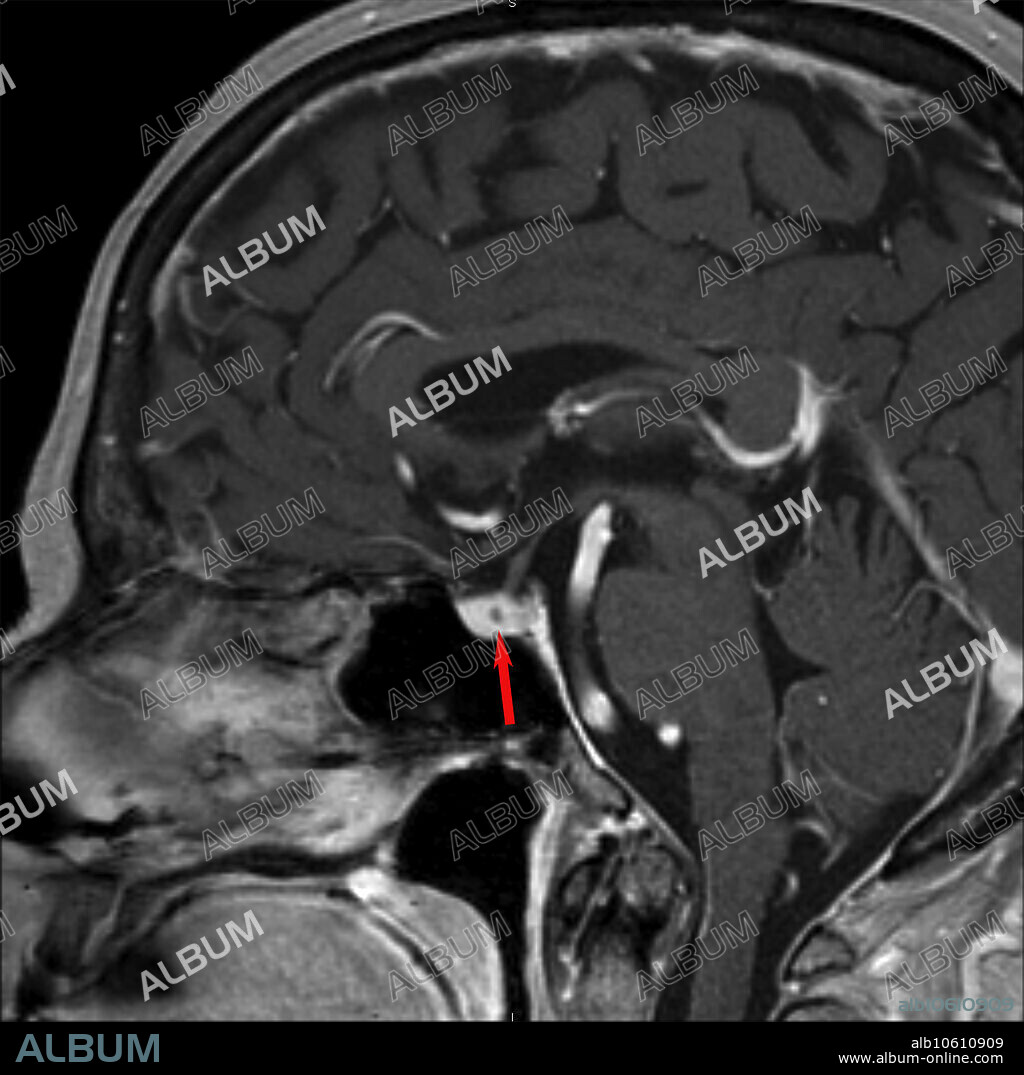

Microadenoma, MRI

78 year old female with abnormal hormone levels (hyperprolactinemia). 3.0T MRI of the sella turcica reveals a 2mm non-enhancing, cystic lesion in the right side of the pituitary gland consistent with microadenoma. 2 mm post gadolinium sagittal T1 image.

Título: Microadenoma, MRI